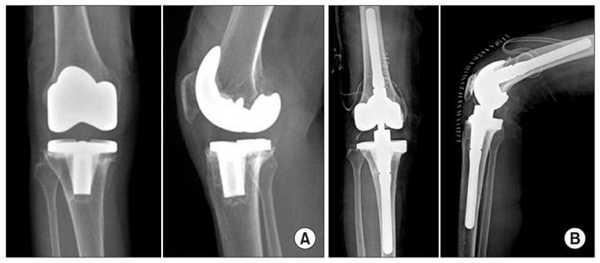

Сравнение двух типов операций.

Две техники операции у одного пациента.

Один пациент, но две разные техники замены коленного сустава: справа — тотальная, слева — одномыщелковая.